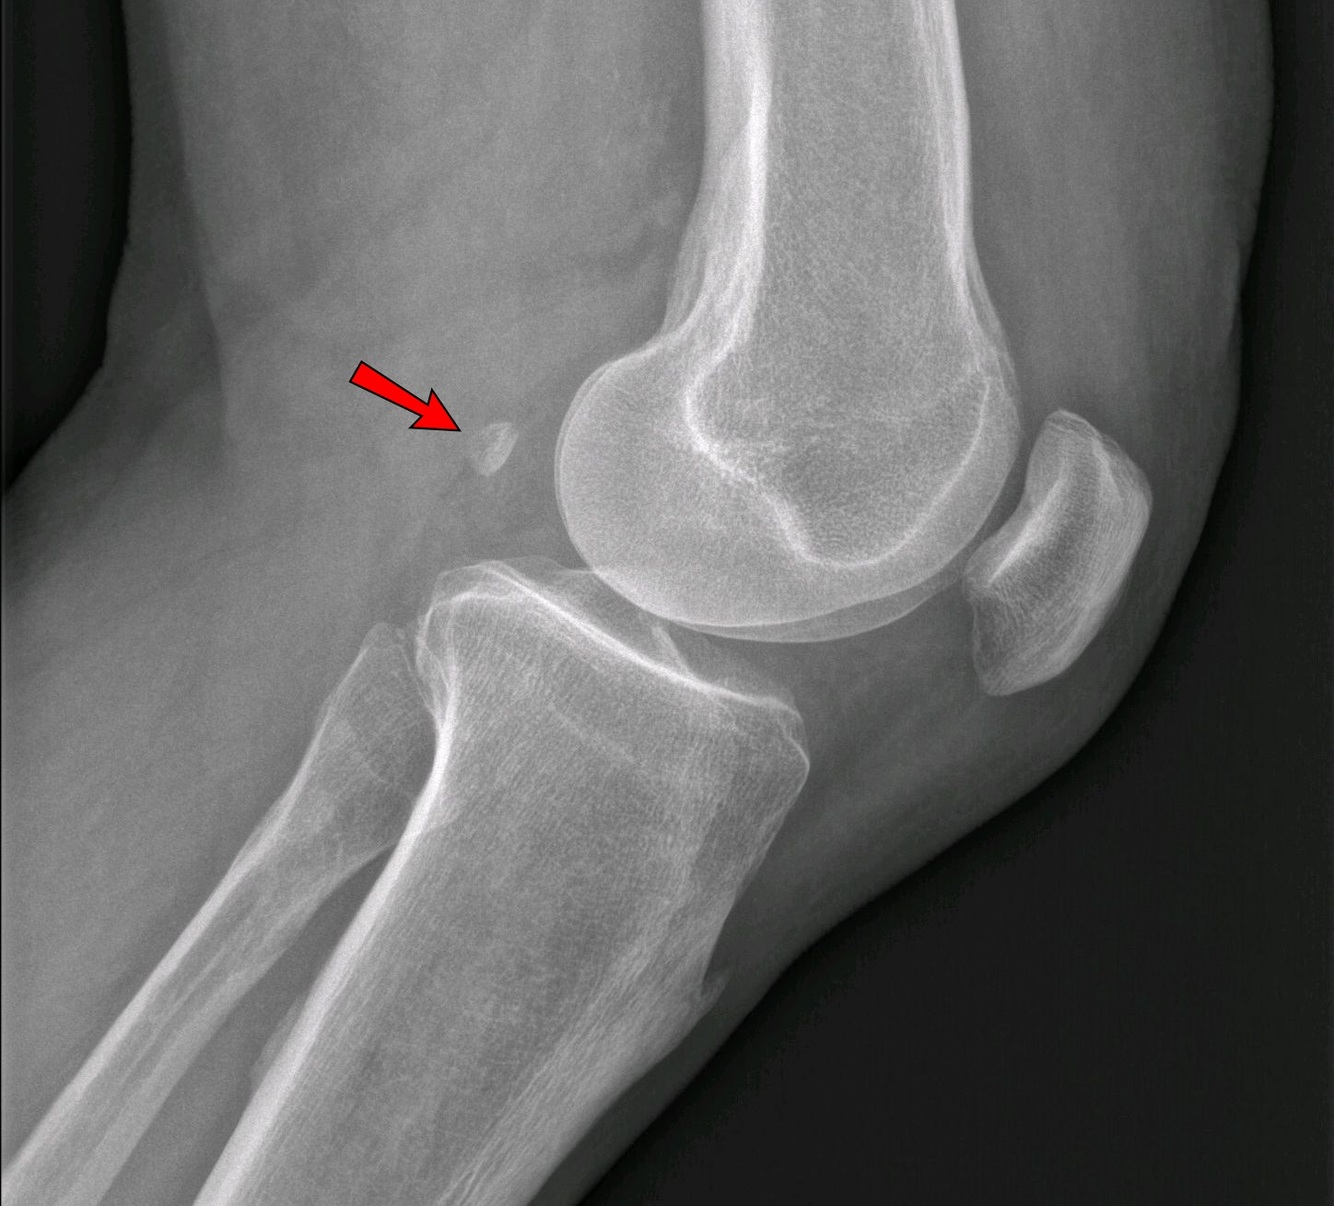

What is the fabella?

Sesamoid within the lateral head of gastrocnemius, often visible posterior to the distal femur